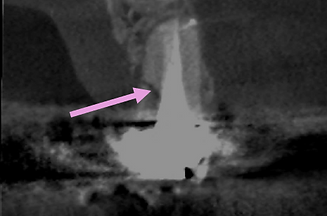

Root fracture at endodontically treated tooth #13.